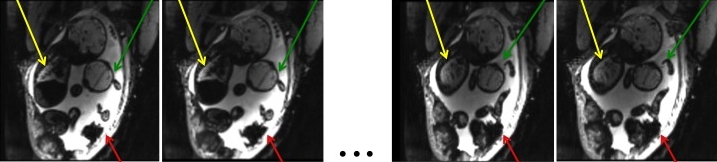

In this paper, we present a robust method for image registration in temporal series of in-utero blood oxygenation level dependent (BOLD) MRI. BOLD MRI is a promising imaging tool for studying functional dynamics of the placenta and fetal brain [1, 2, 3]. It has been shown that changes in fetal and placental oxygenation levels with maternal hyperoxygenation can be used to detect and characterize placental dysfunction, and therefore hold promise for monitoring maternal and fetal well-being [4]. Investigating hemodynamics of the placenta and fetal organs necessitates robust estimation of correspondences and motion correction across different volumes in the dynamic MRI series. Temporal MRI data suffers from serious motion artifacts due to maternal respiration, unpredictable fetal movements and signal non-uniformities [5], as illustrated in Fig. 1. Our approach exploits the temporal nature of the data to achieve robust registration in this challenging setup.